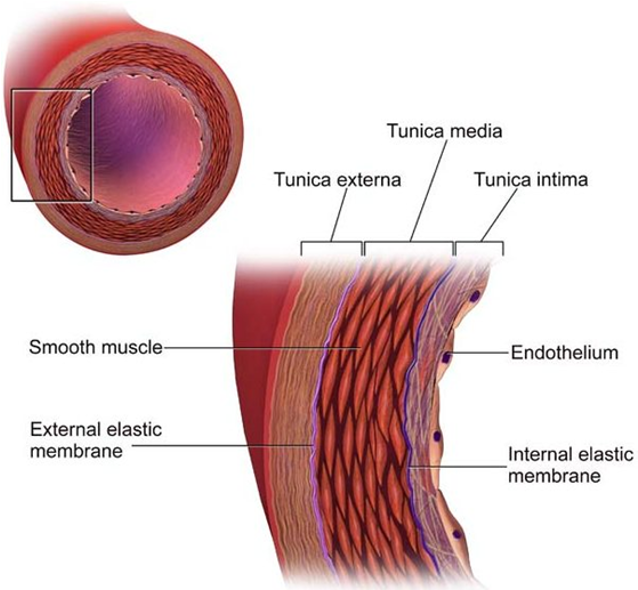

Weakening of the aortic wall

breakdown of the extracellular matrix proteins elastin and collagen (help vessels hold their structure/shape)

Tear in the inner wall of the aorta (intima) causes blood to flow into the middle layer (media) and force the layers apart